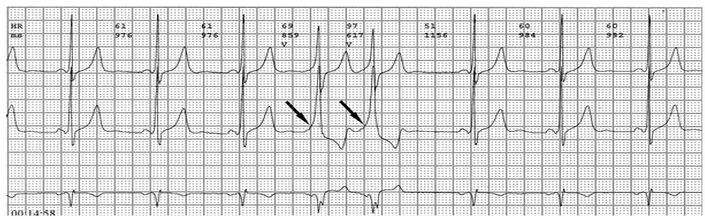

PR间期正常,QRS波群增宽,有预激波。预激综合征室上性心动过速发作时,预激表现大多消失,心电图表现为QRS波群形态正常的室上性心动过速。并发房扑或房颤时,QRS保持预激特征的不少见,心电图表现为QRS波群畸形宽大的房扑或房颤;心室率大多超过200次/分,甚至可达300次/分。房扑时可呈1:1房室传导,并可能辨认房扑波。房颤时心室律不规则,长间歇之后可见到个别QRS波群形态正常(可能为旁路不应期延长,房室结内隐匿传导作用消失后,冲动全部或大部经房室结传导所致),并可能辨认房颤波。心室率极快时,还可伴有频率依赖性心室内传导改变。

(3)QRS波群起始部分变粗钝,称为预激波δ波

(4)继发性ST-TT改变。临床上又分为两型:A型预激:预激波和QRS波群在V1导联向上,其旁道位于左侧房室瓣环周围。B型预激:预激波和QRS波群的主波V1导联向下,在左胸导联V5向上,其旁道位于右侧房室瓣环的周围。